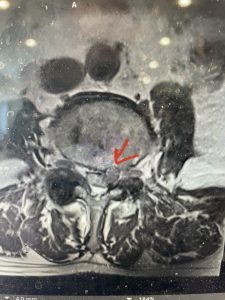

(Figs 3a) Sagittal (a) and Axial (b) T2-weighted lumbar MRI demonstrating severe spinal stenosis L2-5 (arrow)and extruded disc at L3-4 on axial image (arrow)

(Fig 3b)